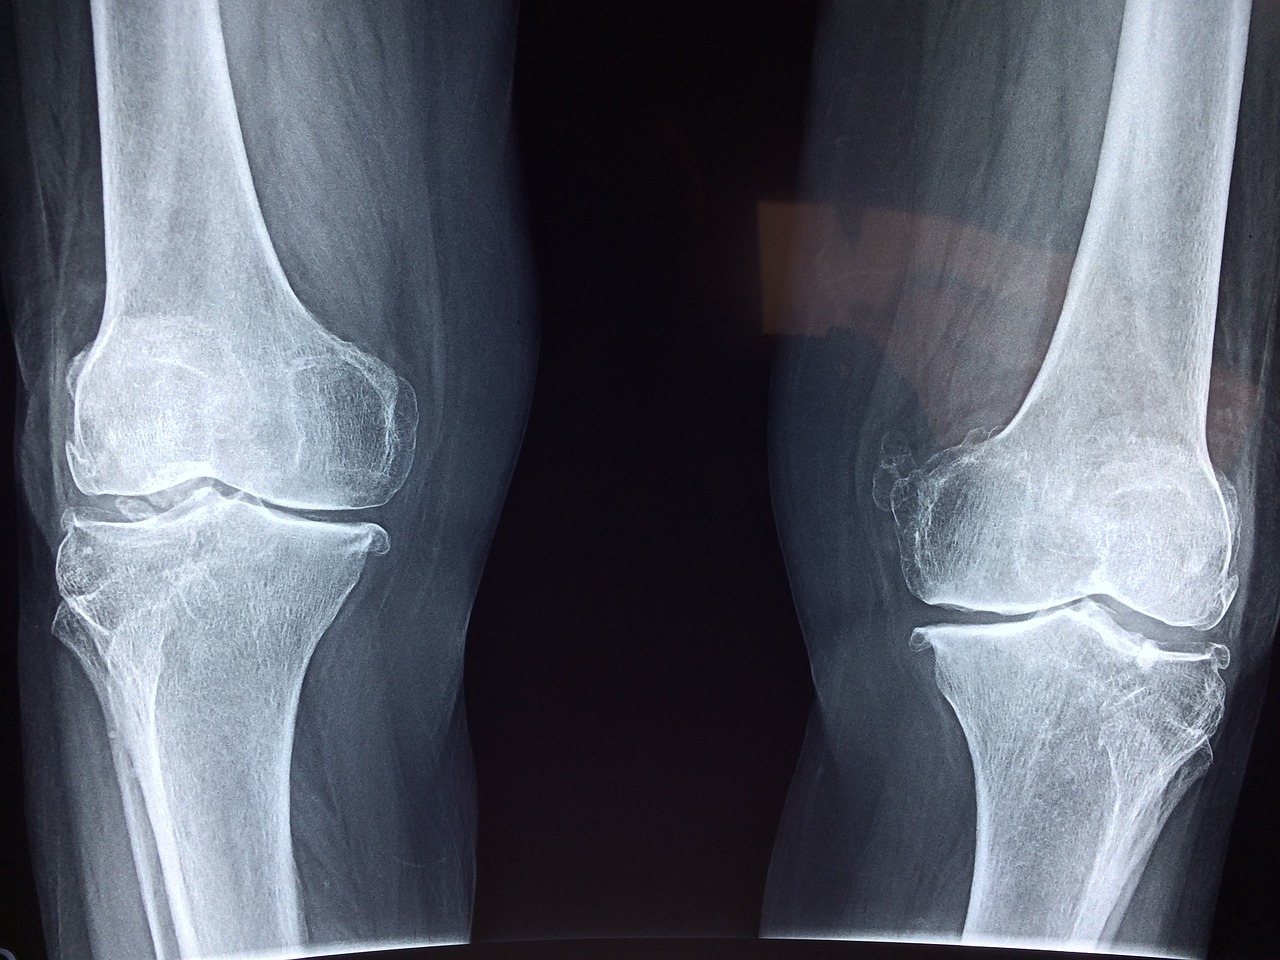

관절 통증과 연골 손상은 나이가 들면서 많은 사람들이 겪는 일반적인 문제들입니다.

콘드로이친 섭취의 주된 이점은 관절염 관리와 통증 경감에 있습니다.

콘드로이친은 연골 내 수분을 유지하고, 이로 인해 연골이 쿠션 역할을 더 잘 할 수 있도록 돕는다고 알려져 있습니다.

따라서 관절과 뼈 사이의 마찰을 줄여주어 관절염으로 인한 통증과 뻣뻣함을 완화시킬 수 있습니다.